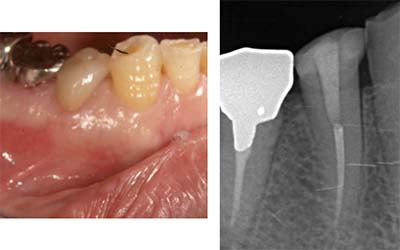

側枝の取り残し

![]() |

| 術前 | 当院にて根充 |

そこで当院では、「成功率に直結する全7工程を、例外なく毎回行う」という標準化(Standardization)を徹底しています。

この標準化こそ、他院で治らなかった歯でも改善する可能性が高い理由です。以下では、当院の全工程を詳しくご紹介します。